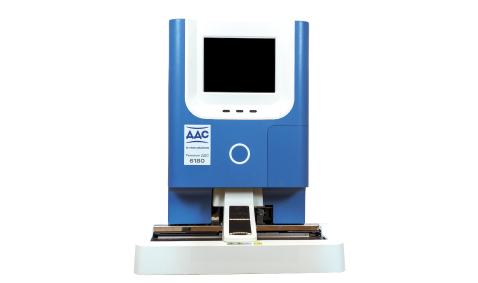

Гематология

URIT-5160

28-параметровый 5-дифф анализатор в компактном исполнении в режиме ручной подачи пробирки